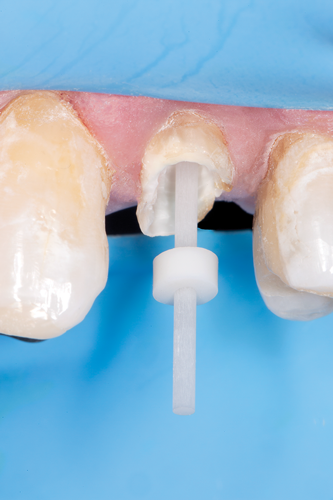

The clear silicone matrix was placed over the posterior segment of the maxillary arch, and an opacious A2-shaded injectable flowable universal resin composite was injected through a small opening above the preparation and fiber post (Figure 20 and Figure 21). The resin composite was cured through the clear resin matrix on the incisal, facial, and lingual aspects for 40 seconds each. Upon removal of the matrix, the excess polymerized composite resin was removed with a #12 scalpel blade, and the incisal sprue was removed using a tapered diamond finishing bur. A round, tapered diamond bur was used to establish the gingival margin (Figure 22) and a needle-shaped finishing bur was used to complete the finishing of the preparation.

Fig 22. The preparation was completed using a tapered diamond bur.

Figure 22